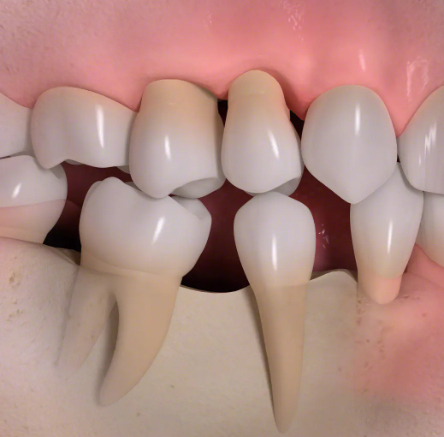

歯を失ったままにしておくと、以下のような見た目・機能・精神面での悪影響が広がっていきます:

■骨が吸収され、歯ぐきが痩せて老けて見える

■隣の歯や噛み合う歯が移動し、噛み合わせが悪くなる

■噛める歯が減り、食事を楽しめなくなる

歯を失ったままにしておくと、日常生活に様々な障害が発生します。

歯を失ったままにしておくと

• 1

歯根が失われると、骨に伝わる力がなくなり、歯を失った部分の骨がやせていきます。

• 2

歯の喪失によって歯が移動し、歯並びがかわってしまう場合があります。

• 3

歯の喪失によって、見た目が悪くなります。

• 4

骨の喪失によって顔の輪郭が変わってしまいます。